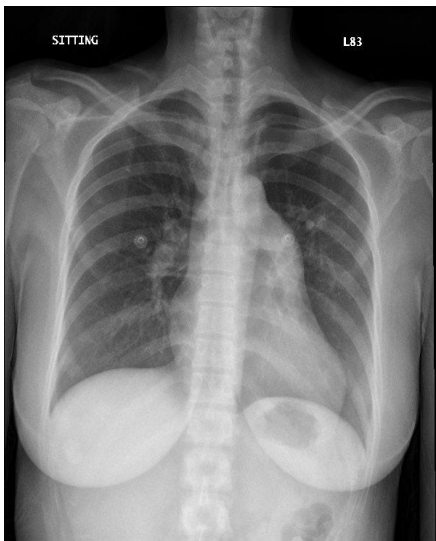

問題二、基於目前的急診檢查結果,請試圖排除或納入某些診斷,您現在剩下哪一些可能的鑑別診斷?有哪些檢查您認為還需要做?病人目前在您手上,您認為他需要什麼立即的治療嗎?

Signs

- Tachypnea (respiratory rate: 30)

- Tachycardia (pulse: 125)

- Temperature : 37.3

- SpO2: 94%

- Bilateral leg pitting edema (1+)

cardiomegaly(-), lung infiltrates(-)